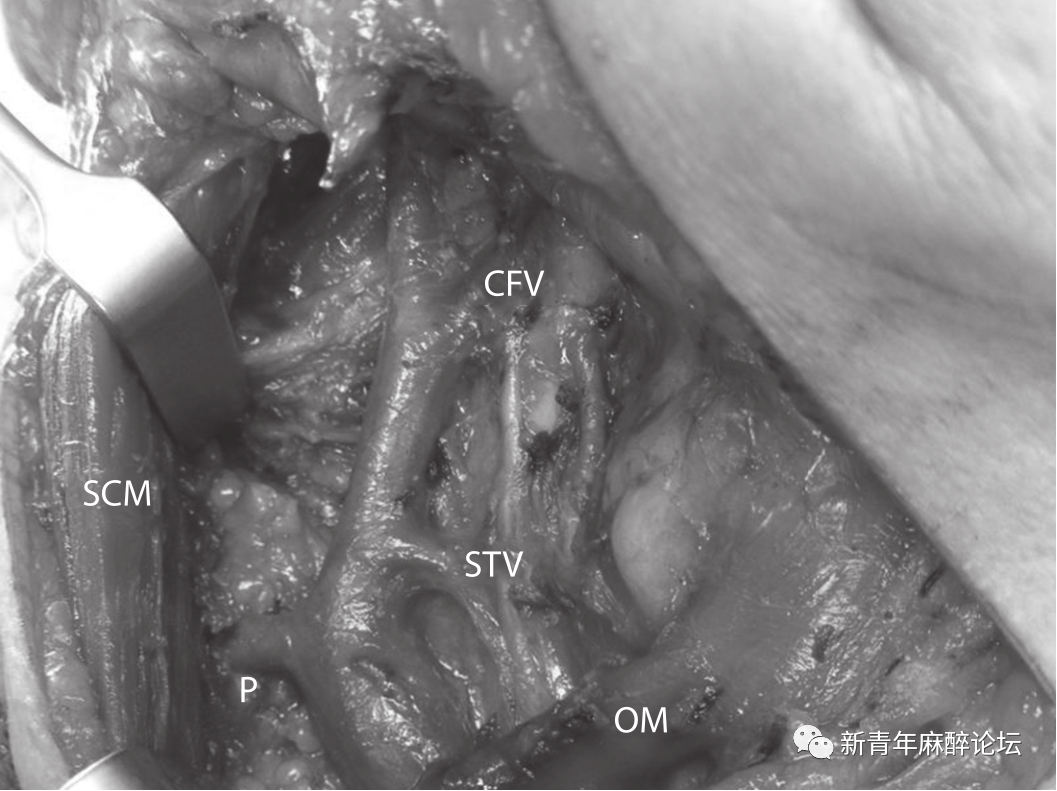

74岁女性,右颈部肿块四周。她之前曾患过左侧口底的鳞状细胞癌,10年前已行包括左侧颈部淋巴结清扫术在内的切除和重建手术。超声和细针穿刺检查显示此肿块为转移性鳞状细胞癌。因此,患者择期行右侧颈淋巴结清扫术(1-4级)。可以看到一条从SCM下方来源的后支向前下侧走向汇入IJV的下1/3(图2)。

图2右颈内静脉后支;CFV-面总静脉、SCM-胸锁乳突肌、OM-舌骨肌、P-后支